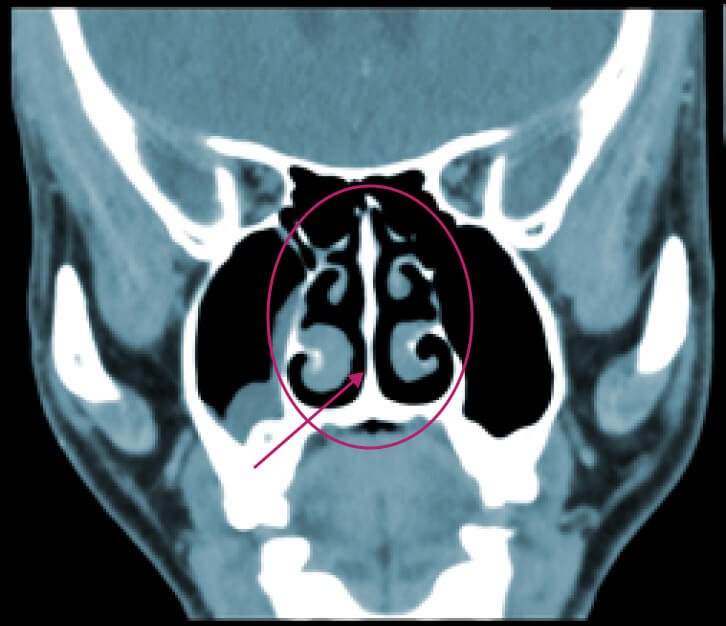

Бүтэц, хэлбэрийн гажигийн жишээ: хамрын таславчийн мурийлт

Харшлын риниттэй өвчтөнүүдэд хамрын таславчийн мурийлт байвал тухайн өвчний явцад сөрөг нөлөө үзүүлэх боломжтой.

Хамрын таславчийн бага зэргийн мурийлт бол хүн амын ихэнхид нь тохиолддог, хэрэв өвчтөнд илэрхий хүндрэл үүсгэхгүй байгаа бол хэвийн гэж үзэж болно. Гэвч хөгжлийн гажиг эсвэл гэмтлийн улмаас үүссэн хамрын таславчийн нилээн их хэмжээний мурийлт нь илүү хүнд үр дагаварт хүргэж болно.

Хамрын таславчийн мурийлт нь хурц хэлбэрийн ринитээс архаг хэлбэрийн ринитэд шилжих хамгийн түгээмэл шалтгаануудын нэг болдог. Үүнээс гадна, иймэрхүү бүтцийн өөрчлөлт нь ургацаг болон уйланхай үүсэхэд нөлөөлж болзошгүй, мөн амьсгалын чадвар буурах, хурхирах, амьсгал түр зогсох (апноэ) зэрэг хүндрэлүүдэд хүргэж болно.